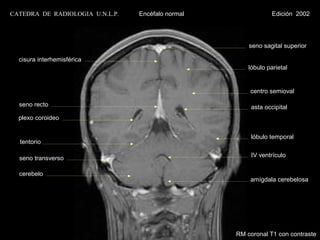

seno sagital superior

cisura interhemisférica

lóbulo parietal

centro semioval

seno recto                                            asta occipital

plexo coroideo

lóbulo temporal

tentorio

seno transverso                                       IV ventrículo

cerebelo

amígdala cerebelosa

RM coronal T1 con contraste